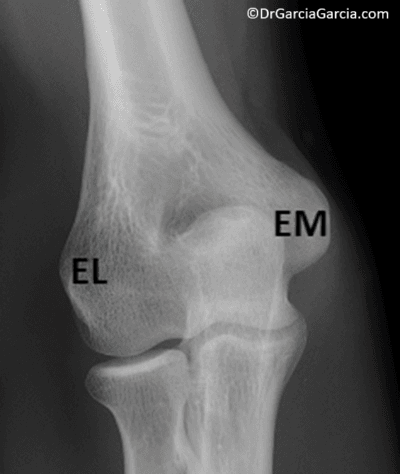

Los epicóndilos son las prominencias palpables a los lados del codo, una lateral y la otra medial (también llamada epitróclea); son los sitios de origen de los músculos del antebrazo que intervienen en la pronosupinación y la flexión-extensión de muñeca y dedos.

En el epicóndilo lateral se originan los músculos que cumplen la función de extensión de muñeca y dedos y la supinación del antebrazo. El medial es el sitio de origen de los flexores de carpo y dedos y pronadores del antebrazo. Justo distal al epicóndilo medial está la inserción humeral del ligamento colateral cubital conformado por tres haces1,2.

Figura 1. Radiografía AP del codo. EL: epicóndilo lateral, EM: epicóndilo medial.